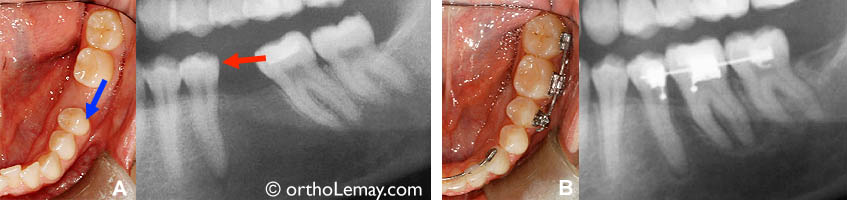

Avec l’utilisation d’une mécanique et des forces appropriées, il est possible de déplacer des dents sur des distances importantes (jusqu’à plus de 10 mm), comme dans ce cas où des molaires ont été avancées pour fermer un espace.

Lorsque les dents commencent à se déplacer, la zone du ligament parodontal (autour des dents) visible sur une radiographie et devient plus large (ligne foncée le long des racines). La ligne plus pâle est une couche d’os alvéolaire plus dense.